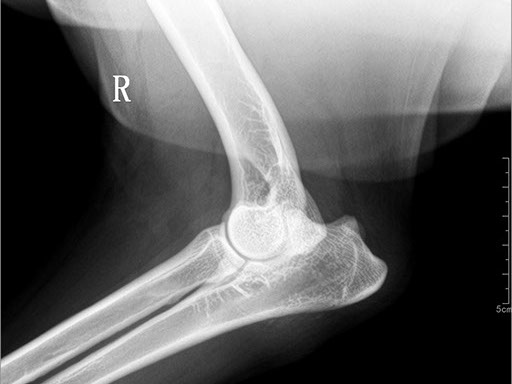

ЦИФРОВОЙ РЕНТГЕН В ВЕТЕРИНАРИИ